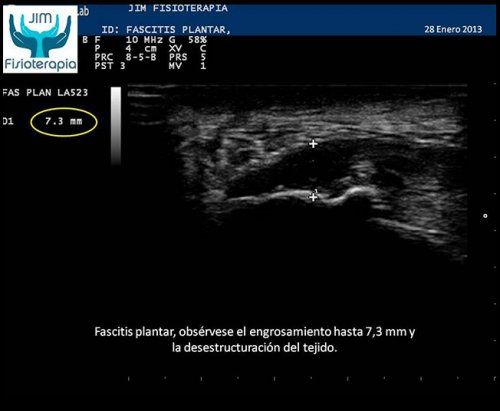

Tratamiento de la fascitis plantar mediante EPI® en Madrid

Mujer de 75 años de edad, sin actividad deportiva y aquejada de sobrepeso. Presenta una fascitis plantar de cinco meses de evolución, extremadamente dolorosa e incapacitante; manifiesta haber sido tratada en su localidad mediante microonda, ultrasonido y masaje sin mejoría.[...]